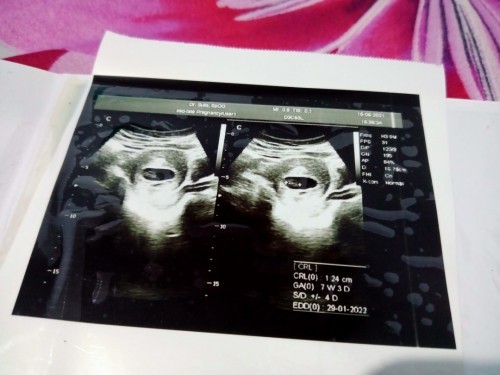

Kandungan saya lemah keluar flek sudah 22 hari Bagaimana solusi untuk mengatasi masalah kehamilan

Kandungan lemah keluar darah

saya juga dari sebulan yg lalu sampai skrg flek terus,tapi alhamdulillah janin sehat,,dikasih obat penguat sama cek ke spog 2minggu sekali ,,banyak istirahat bun dan positif thinking tetep semangat pertahanin buah hatinya